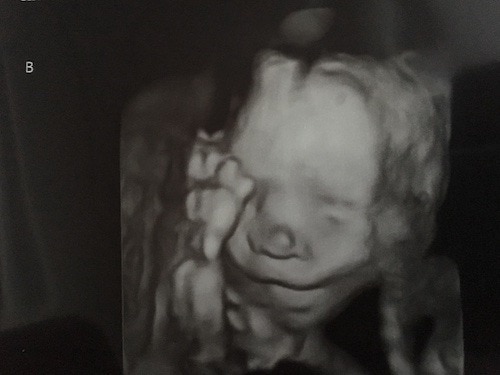

Ultrasound Photos at 22 Weeks Pregnant With Twins